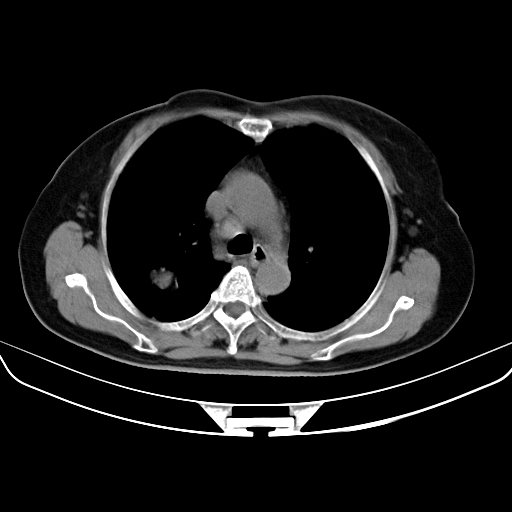

以下是引用zjzjr在2007-3-23 13:28:00的发言:[br]右肺上叶后段可见一结节状高密度影,可见毛刺征,胸膜凹陷征及血管导入征,纵隔内可见肿大淋巴结影.考虑右肺上叶周围型肺癌伴纵隔淋巴结转移.

以下是引用zjzjr在2007-3-23 13:28:00的发言:[br]右肺上叶后段可见一结节状高密度影,可见毛刺征,胸膜凹陷征及血管导入征,气管前腔静脉后可见肿大淋巴结影.考虑右肺上叶周围型肺癌伴纵隔淋巴结转移.